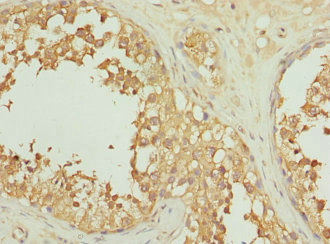

Immunohistochemistry of paraffin-embedded human testis tissue using CSB-PA011721ESR1HU at dilution of 1:100